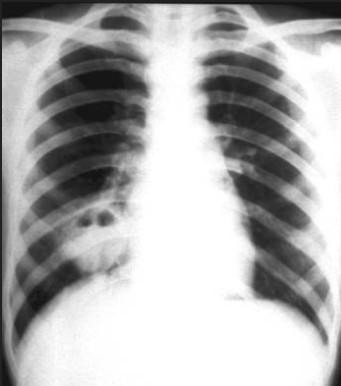

X线检查[编辑 | 编辑源代码]

肺脓肿的X线表现根据类型、病期、支气管的引流是否通畅以及有无胸膜并发症而有所不同。

吸入性肺脓肿在早期化脓性炎症阶段,其典型的X线征象为大片浓密模糊炎性浸润阴影,边缘不清,分布在一个或数个肺段,与细菌性肺炎相似。脓肿形成后,大片浓密炎性阴影中出现圆形透亮区及液平面。在消散期,脓腔周围炎症逐渐吸收,脓腔缩小而至消失,最后残留少许纤维条索阴影。慢性肺脓肿脓腔壁增厚,内壁不规则,周围炎症略消散,但不完全,伴纤维组织显著增生,并有程度不等的肺叶收缩,胸膜增厚。纵隔向患侧移位,其他健肺发生代偿性肺气肿。

血源性肺脓肿在一肺或两肺边缘部有多发的散在小片状炎症阴影或边缘较整齐的球形病灶,其中可见脓腔及液平面。炎症吸收后可呈现局灶性纤维化或小气囊。

并发脓胸者,患侧胸部呈大片浓密阴影;若伴发气胸则可见液平面。

侧位X线检查,可明确脓肿在肺脏中的部位及其范围大小,有助于作体位引流或外科治疗。